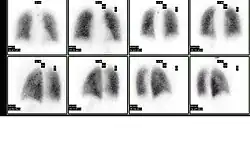

Normal pulmonary ventilation and perfusion (V/Q) scan. The nuclear medicine V/Q scan is useful in the evaluation of pulmonary embolism.

Normal pulmonary ventilation and perfusion (V/Q) scan. The nuclear medicine V/Q scan is useful in the evaluation of pulmonary embolism. -